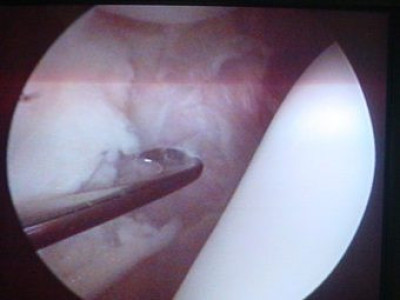

Luxación Habitual de Rótula

Envíado por Dr. Eduardo E. Martínez Melara